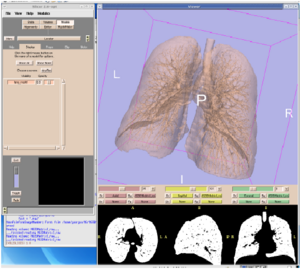

- 3.23 Optimizing Parameters of an Open-source Airway Segmentation Algorithm using Different CT Images